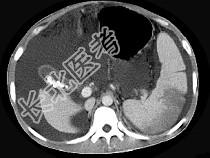

- 单项选择题患者男,29岁, 乙肝病史10余年,腹胀, 有移动性浊音,影像检查如图, 最全面的诊断是 ( )

A、肝硬化

B、肝硬化腹水

C、肝硬化腹水、脾梗、胆囊结石

D、大网膜膈下间位及脾梗

E、胆结石及脾梗